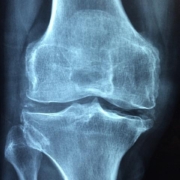

Supportive Devices: Consider using braces or supports if you have a history of injuries or weak joints.